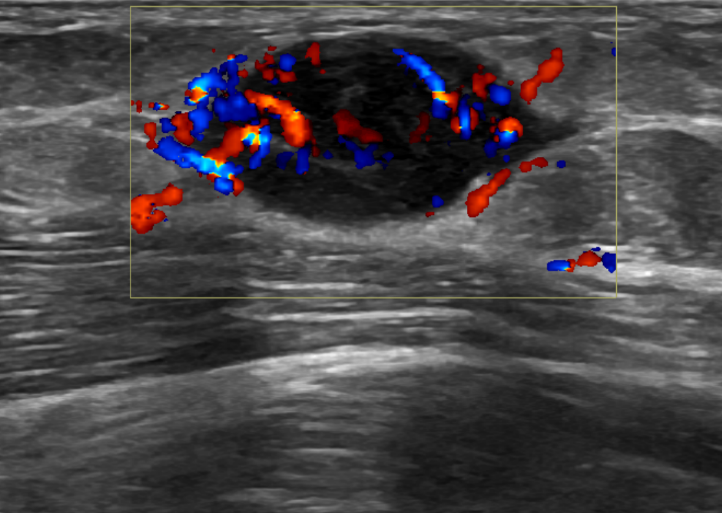

3. Neuroma